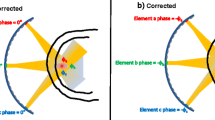

For 3D acoustic pressure field mapping, the HIFU focus was electronically steered relative to the fixed fiber tip location. First, a relative coarse scan within a larger volume (5 × 5 × 20 mm3) was performed in a step size of 2 mm along the beam path (Z-axis) and 0.5 mm across the beam path (X- and Y-axes). This procedure was repeated three times to assess MRI-assisted focus alignment relative to the fiber. The time needed to perform measurements at each location was 2.8 s for initialization, sonication, hydrophone measurement, and a wait time for exposure and measurement preparation at the next location. After fiber tip localization based on the coarse scan, the transducer was repositioned with its focus aligned at the identified fiber tip location. Then, a finer scan was performed within a smaller volume (1.5 × 1.5 × 15 mm3) with step sizes of 1.5 mm and 0.15 mm along and across the beam path, respectively. After precise fiber tip localization through the finer scan, acoustic pressure waveforms at the focus were acquired for nominal acoustic powers ranging from 50 W to 500 W at 50 W intervals. Throughout the experiments, the HIFU transducer was operated at 1.2 MHz with a pulse repetition frequency of 12 Hz and a pulse length of 40 cycles. A custom MATLAB program (version 7.14, The Mathworks Inc., Natick, MA, USA) integrating MatHIFU [14], a MATLAB toolbox for real-time control of the Sonalleve MR-HIFU system, was used to control the HIFU beam steering, transducer positioning, HIFU pulse parameters, and hydrophone signal acquisition.

The main limitation of the electronic beam steering-based hydrophone measurement method is that all phased array transducers have limited steering range, above which a pressure reduction occurs at the focus (Fig. 4). We overcame this limitation by integrating electronic beam steering with the MRI-assisted alignment of the nominal transducer focal point at the fiber tip using the MR-HIFU therapy planning software, which allowed us to localize the fiber tip with the maximum steering distances of 2.5 mm in the radial direction and 10 mm in the axial direction. Within such relatively small steering distance, the pressure reduction was less than 4.7%, which is within the measurement uncertainty of typical hydrophone measurement [16, 17]. When large steering ranges are required, the proposed method can still be used when a calibration of the pressure reduction similar as shown in Fig. 4 is performed. From the calibration curve, we can calculate the percentage of pressure reduction at each steering distance. Each pressure measured using the beam steering method can then be compensated using the corresponding percentage of pressure reductions to estimate the actual pressure at each spatial location of the acoustic field.